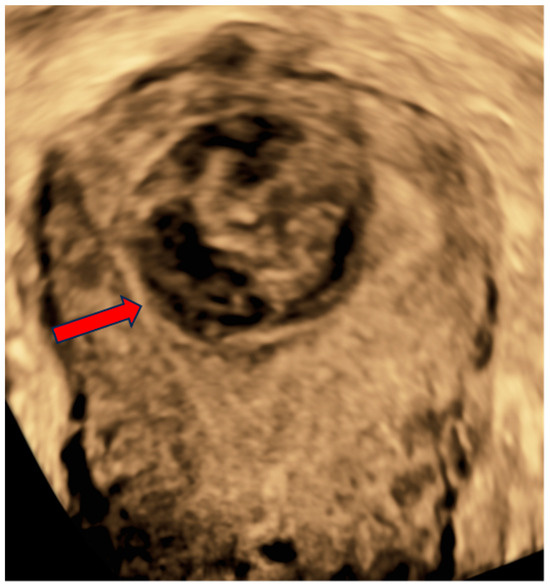

On examination, there were not any palpable masses in the abdomen. The uterine corpus was not enlarged, not painful, and mobile. The cervix was normal-looking, although there was some bloody discharge and blood clots in the vagina. The adnexa were not palpable per vaginal examination. A two-dimensional/three-dimensional transvaginal ultrasound (2D/3D-TVS) examination using a Voluson E10 (GE Healthcare Ultrasound, Milwaukee, WI, USA) revealed a single oval-shaped submucosal lesion located within the uterine fundus, protruding into the uterine cavity (Figure 1 and Figure 2). The lesion measured 32.2 × 29.4 mm and had mixed echogenicity and well-defined borders without acoustic shadow. No calcifications or cystic areas were visible in the lesion. The uterus was anteverted, measuring 64 × 68.9 mm, with a thin endometrium and signs of adenomyosis within the myometrium. The adnexa was normal bilaterally, and there was no fluid in the Douglas pouch. The examination was performed by level three experts according to the European Federation of Societies for Ultrasound in Medicine and Biology (EFSUMB, www.efsumb.org, accessed on 20 October 2024).

Figure 2.

A coronal plane view of the patient’s uterus obtained with a 3D-TVS. The lesion (red arrow) protruding from the uterine fundus exerts a visible mass effect on the endometrial cavity.

There are no ultrasound features that could specifically indicate malignancy in uterine smooth-muscle tumors [11]. Distinguishing STUMP from leiomyosarcoma based on imaging methods is virtually impossible. However, due to the widespread availability of ultrasound, these lesions are often visualized and described using this method. The most common morphological ultrasound features indicating the risk of malignancy are irregular borders of the lesion, irregular cystic areas, non-uniform echostructure, mixed echogenicity, and rich vascularization [21]. Malignant lesions are more commonly single, bigger than benign, and exhibit rapid growth.

On the contrary, visualization of normal myometrium and acoustic shadow is more typical for benign lesions [21]. The presence of calcifications is not indicative of the malignancy of the lesion; however, some authors suggest they are more common in benign leiomyomas [22]. In general, ultrasonography is not a perfect method to differentiate benign and malignant lesions with moderate specificity and sensitivity [23]. However, the use of these ultrasound features in combination with clinical data, such as age and presence of symptoms, in the form of diagnostic algorithms can be effective as a sensitive method of selecting patients at risk for STUMP or sarcoma with high negative predictive value, but at the cost of significantly lower specificity [21]. It is particularly challenging to differentiate sarcomas and STUMPs from degenerating leiomyomas with heterogeneous echogenicity and central necrosis. In our case, the ultrasonographic appearance was not characteristic of malignant lesions, although the lack of acoustic shadowing, mixed echogenicity of the lesion and rich vascularization are more frequently seen in STUMPs and leiomyosarcomas [21].